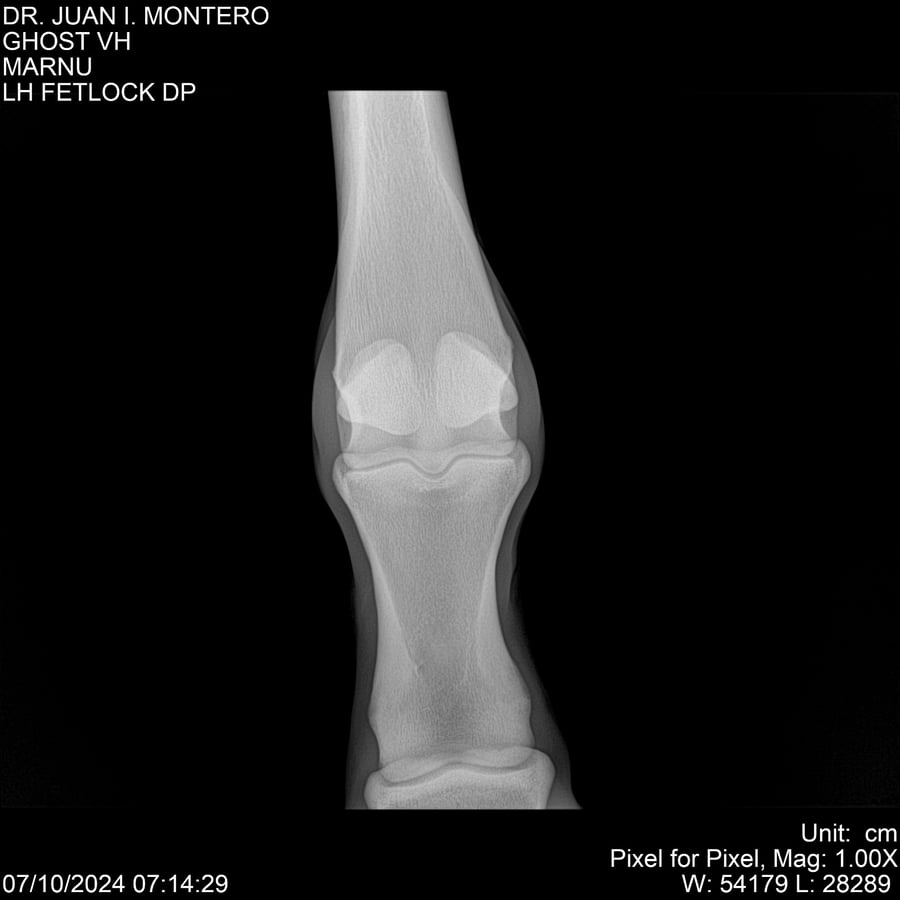

LOTE 15, GHOST VH 🔥 🔥 🔥 Lote Anterior Volver al remate Lote Siguiente Ficha Contacto Montevideo - Ficha del Lote Identificador: #282525 Categoría: Yeguarizos Montevideo - 69 Visualizaciones ClicData Contacto Empresa: Abelenda N. R., Walter Hugo Nombre*: Teléfono* : E-mail* : Mensaje Enviar Registrese gratis Este contenido Exclusivo está disponible sólo para usuarios registrados Ingresar